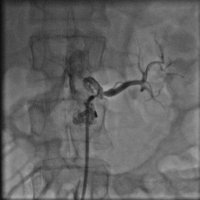

44 yaşında şeker hastalığı olan hastamız dirençli yüksek tansiyon şikayetiyle bize başvurdu. Herhangi bir sebep bulunamayan hastamız 2 yıldan beri cesitli ilaçlar kullanmasına rağmen tansiyonunun düşürülemediğini söylüyordu. Yaptiğımız detaylı muayene ve tetkikler sonucu böbrek damarının tıkalı olduğunu tesbit ettik ve yaptıgımız stent işlemi sonrasında hastamız normal tansiyon değerleriyle taburcu edildi..